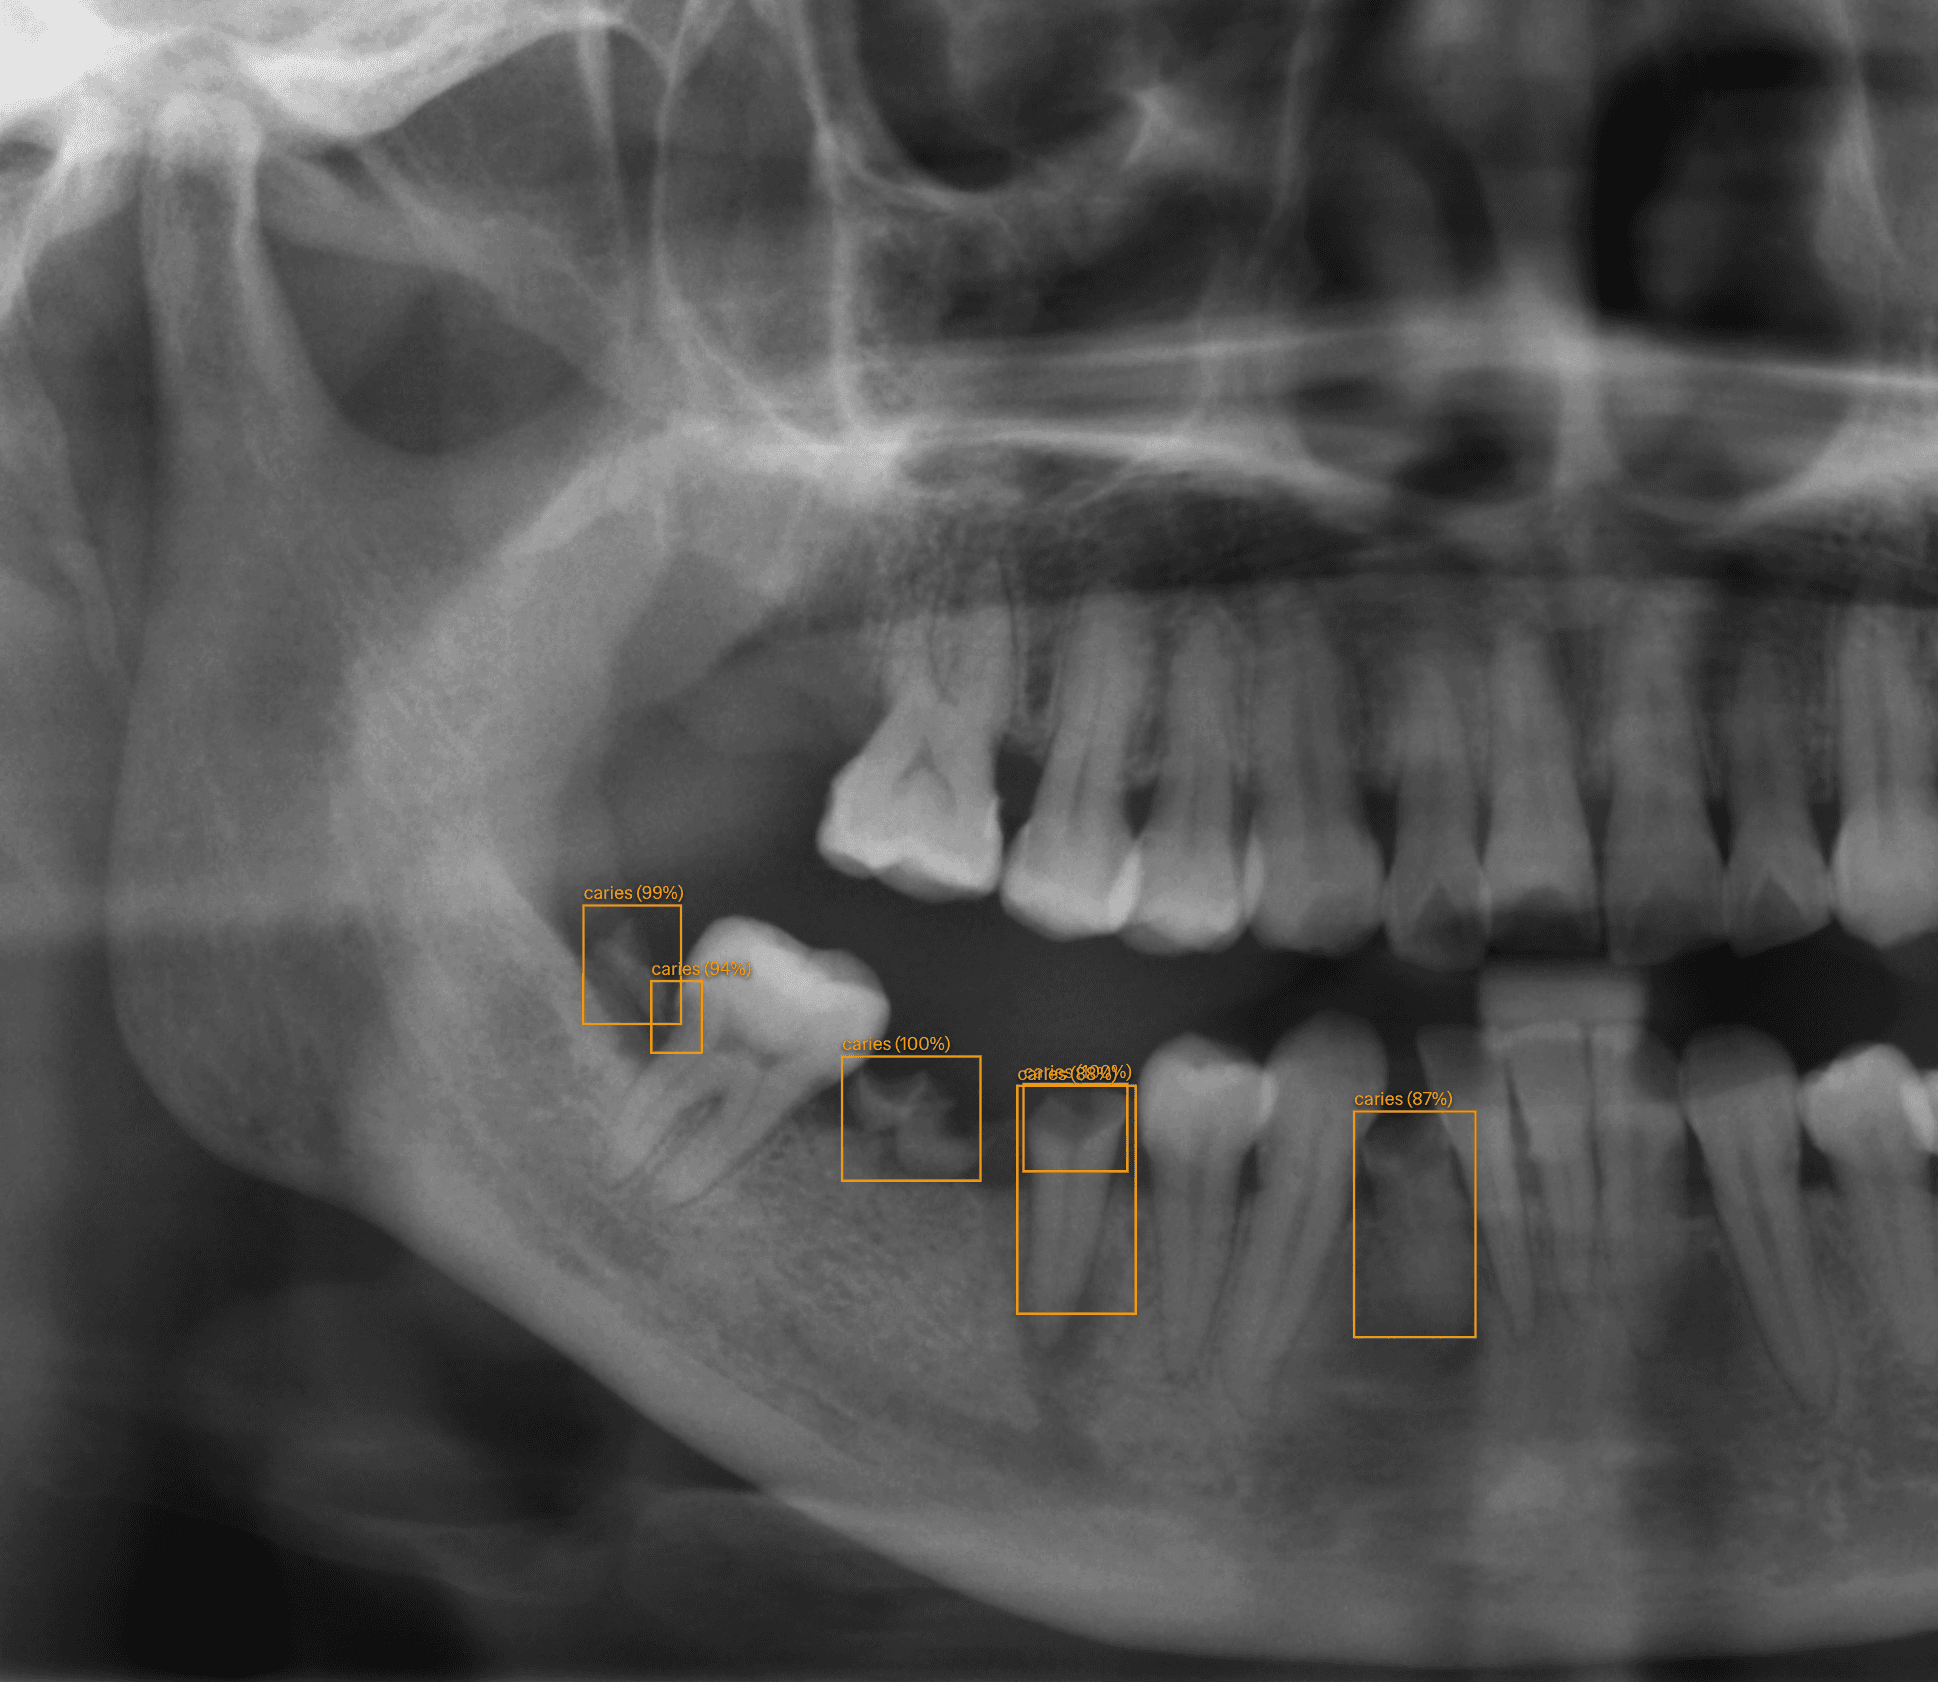

Diagnostic assisté par IA

Gagnez un précieux temps lors de vos consultations. L'IA de SmiloLink identifie automatiquement les caries, les lésions apicales et d'autres pathologies sur vos radiographies panoramiques et rétroalvéolaires.